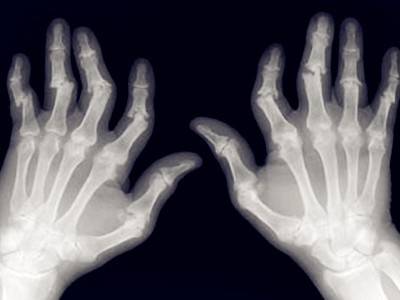

类风湿性关节炎的影像与病理

图片尺寸944x721